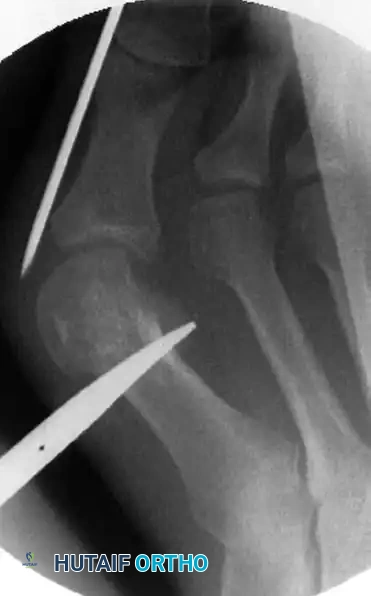

يتم تأكيد الشكل النهائي للقدم وموقع السلك المعدني باستخدام الأشعة السينية. يعتبر التصحيح ناجحا عندما تكون العظام مصطفة بشكل مستقيم وسليم.

التأكيد النهائي لشكل القدم بالأشعة